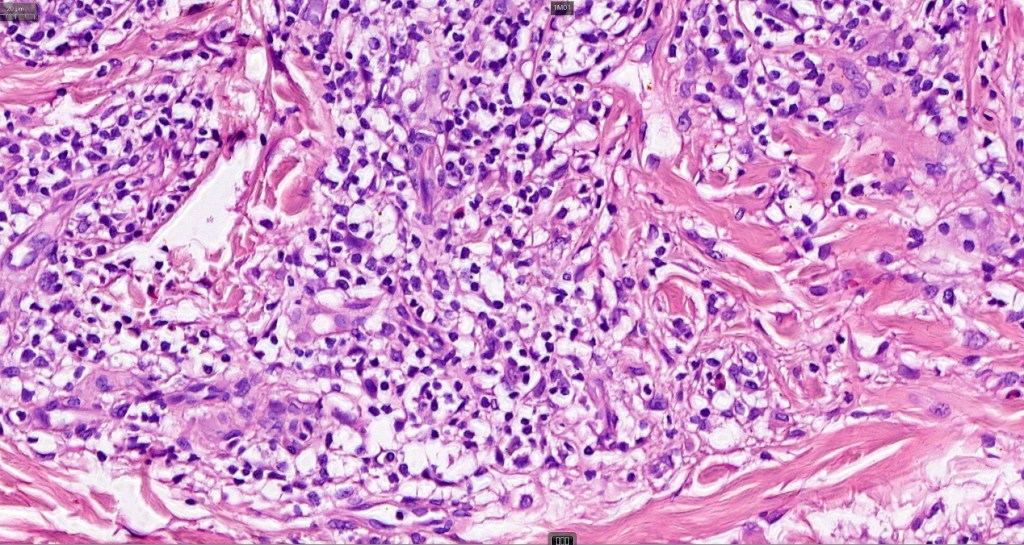

. Late lesions are charcterized by epidermal atrophy, papillary dermal fibrosis, pigment incontinence & a perivascular or interstitial lymphocytic infiltrate

•CD8+ & CD20+ lymphocytes